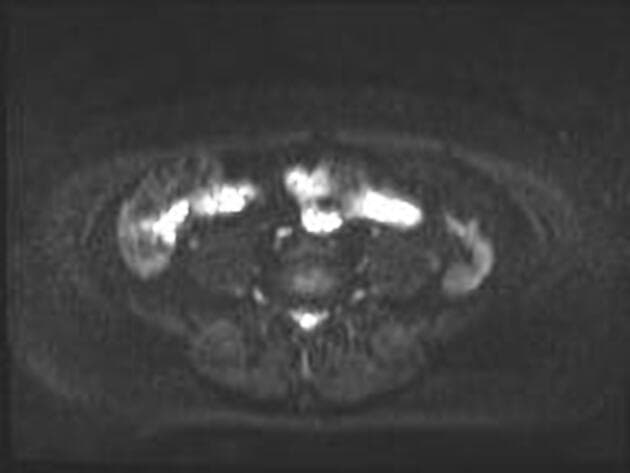

- Ghi nhận bệnh lý hạch (lymphadenopathy) có tín hiệu bất thường, đường kính trục ngắn tối đa (SAD) 8 mm, nằm ngay dưới vị trí phân nhánh của tĩnh mạch chậu trong trái. Hạch này biểu hiện hạn chế khuếch tán (restricted diffusion) trên hình ảnh khuếch tán (DWI) và có tăng quang sau tiêm thuốc cản quang (post-contrast enhancement).

Trường hợp này biểu hiện ung thư cổ tử cung lan rộng tại chỗ với bằng chứng rõ ràng về xâm lấn parametrium và hạch chậu di căn, đáp ứng tiêu chuẩn giai đoạn IIIC1 theo hệ thống FIGO. Hạch vùng chậu trái có hạn chế khuếch tán và tăng quang sau tiêm thuốc, hỗ trợ chẩn đoán ác tính. Kết quả giải phẫu bệnh xác nhận ung thư biểu mô tế bào vảy kiểu sản sừng, dạng tổ chức học phổ biến nhất của ung thư cổ tử cung. Các tổn thương gan và thận lần lượt phù hợp với u mạch gan và nang vỏ thận đơn giản – đều là tổn thương lành tính, nhấn mạnh tầm quan trọng của việc định tính tổn thương chính xác để tránh phân giai đoạn quá mức. Việc phân giai đoạn chính xác định hướng điều trị, với giai đoạn IIIC1 thường được điều trị bằng hóa xạ trị thay vì phẫu thuật.